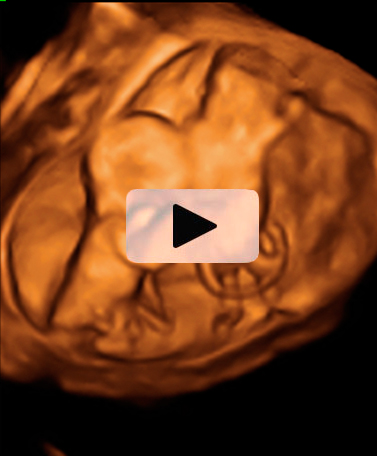

Ecografía semana 11: Bebé moviéndose en el útero

El bienestar fetal de este bebé de 11 semanas de gestación parece evidente a juzgar por su movimiento de brazos y piernas. Esta ecografía 4D ofrece el "baile" de este pequeñín, que está finalizando su primer trimestre de embarazo.

Ecografía en 4D de feto de 11 semanas moviéndose

Feto de 11 semanas de gestación con brazos y piernas en movimiento continuo dentro del útero materno. No se aprecian las extremidades con nitidez debido al "corte" de imagen que selecciona el ecografista.